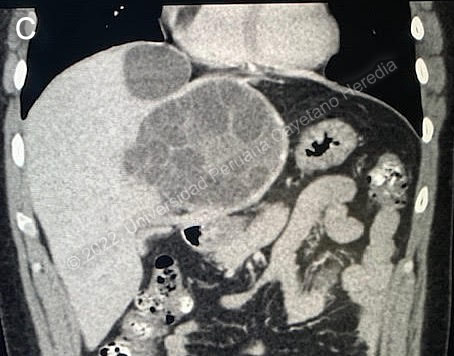

![]() Discussion: After the procedure an abdominal CT scan was taken (Image C), which shows two cystic lesions in the liver with a heterogeneous content; the larger one has daughter cysts inside. The patient was treated with broad spectrum antibiotics and albendazole for 4 weeks and scheduled for surgery. A laparoscopic left hepatectomy was performed, a large cyst was observed broken into the biliary tract at four different points. The fistulas were sutured and a capitonage and closure with omentum were performed. The patient did not have an allergic reaction with the rupture of the cyst. Liver hydatid cyst rupture is classified into three types: a) contained rupture, when the endocyst (acellular multilaminated membrane and nucleated internal germinal membrane) ruptures but the content is confined within the pericyst (compressed host organ parenchyma), b) communicating rupture, when cyst content escapes usually into the biliary tract because the pericyst incorporates biliary branches as it expands, and c) direct rupture when both endocyst and pericyst tear and the full content spills into the abdominal cavity (AJR 1988;150:1051-3). When the cyst communicates with the biliary tract it may involve the common hepatic duct, lobar branches or small intrahepatic branches, the latter are most commonly involved. Small communications between liver cysts and the biliary tree seem to be common (40-90%) and are usually asymptomatic, but large tears are less frequent (5-10% of these) causing biliary tree obstruction and potentially serious complications such as cholangitis, hepatic abscesses, acute cholecystitis, acute pancreatitis and even biliary cirrhosis (Br J Surg 1971;58:228-32; AJR 1982;139:699-702). CT can help identifying the communication between the liver cyst and the biliary tract by showing the defect or discontinuation of the cyst or indirectly by showing linear and irregular tracts inside the biliary tract. Multidetector CT enhances the view of the common bile duct and may be used as an adjunct diagnostic technique in cases of suspected major tears into the biliary tract (Abdom Imaging 2011;36:433-7). ERCP may be used to remove the contents of the cyst, as in this case, but usually surgical exploration is needed. Human hydatid disease secondary to Echinococcus granulosus is caused by the larval form of this dog tapeworm. Humans ingest the tapeworm eggs in environments contaminated by canine feces and become accidental intermediate hosts. Sheep are the normal intermediate hosts. In general, disease is diagnosed in adulthood as larval cysts expand slowly over years or decades, becoming symptomatic as they impinge on other structures by virtue of their size. The cysts contain hundreds of viable protoscolices capable of becoming adult tapeworms upon ingestion by a definitive host such as the dog. The cyst wall is composed of a 1 mm thick acellular multilaminated membrane, followed by the nucleated internal germinal membrane that is about 0.1 mm thick. The internal germinal membrane lining the cyst produces new protoscolices on an ongoing basis and may also give rise to daughter cysts inside the original cyst. Each protoscolex is capable of becoming a new daughter cyst should the original cyst rupture or be ruptured. Cystic hydatid disease due to E. granulosus is common in sheep and cattle raising areas worldwide. Most primary infections involve a single cyst. In adults, 65% of solitary cysts are found in liver, 25% in lung and the rest in a wide variety of other organs including kidney, spleen, heart, bone and brain. In patients with a pulmonary cyst, approximately 18% will also have a hepatic cyst. The majority of patients with hydatid cysts have no or mild eosinophilia. This patient had near to hypereosinophilia (1483 eos/uL). Eosinophilia may occur in asymptomatic patients but is more common after surgery or when the cyst ruptures, as in this case. The cyst with the daughter cysts had ruptured into the biliary tract but not into the peritoneal cavity, so there was no intraabdominal seeding of the cyst contents; during surgery there was also no obvious intraperitoneal seeding. Cysts opened to the biliary tree, bronchi, abdominal cavity or urinary tract should be treated surgically, praziquantel (a very effective protoscolicidal agent) or albendazole is given postsurgically in case there was any inadvertent secondary seeding. The finding of characteristic cysts and membranes in the main duct was diagnostic, so there was no need for doing a serology, which may be negative in intact cysts. Albendazole was given for four weeks prior to surgery, presumably trying to sterilize the cyst before surgery. The presence of daughter cysts decreases the effectiveness of this measure. One of the concerns is the use of albendazole in a patient with elevated transaminases, because it is one of its side effects in addition to leukopenia. In this case the elevated transaminases were most likely due to the cholangitis, and albendazole administration was apparently well tolerated. The patient was referred to us because he was found to have a remaining liver cyst of less than 3 cm in diameter. In his laboratory tests, the eosinophil count was 230/uL and ALT was 17 U/L. He started medical therapy with albendazole. Response of small cysts to albendazole is usually good. |